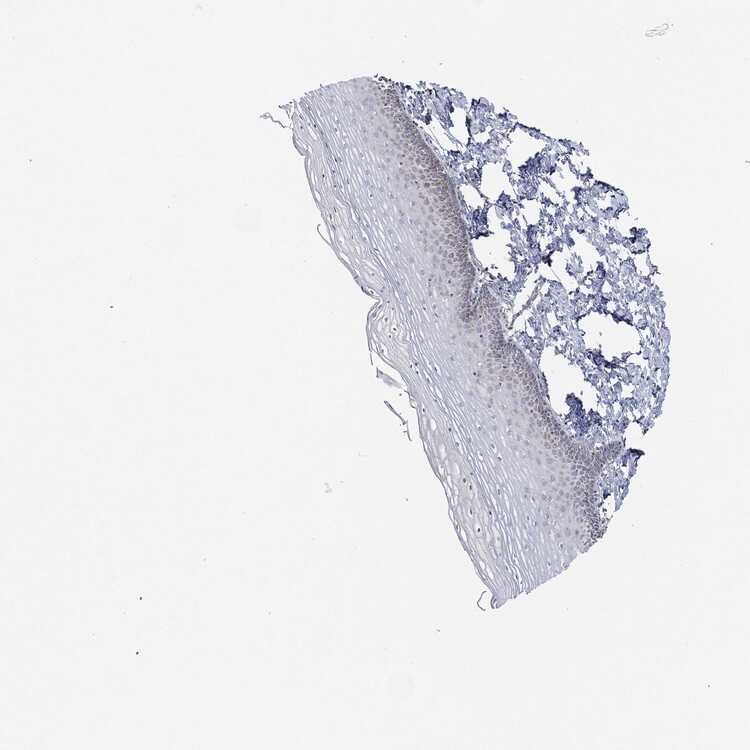

CERVIX - Antibody stainingi

Antibody staining in the annotated cell types in the current human tissue is reported as not detected, low, medium, or high, based on conventional immunohistochemistry profiling in selected tissues. This score is based on the combination of the staining intensity and fraction of stained cells.

Each image is clickable and will lead to virtual microscopy that enables deeper exploration of all samples and also displays staining intensity scores, fraction scores and subcellular localization as well as patient and tissue information for each sample.

Antibody HPA074218

Glandular cells Low

Squamous epithelial cells Low